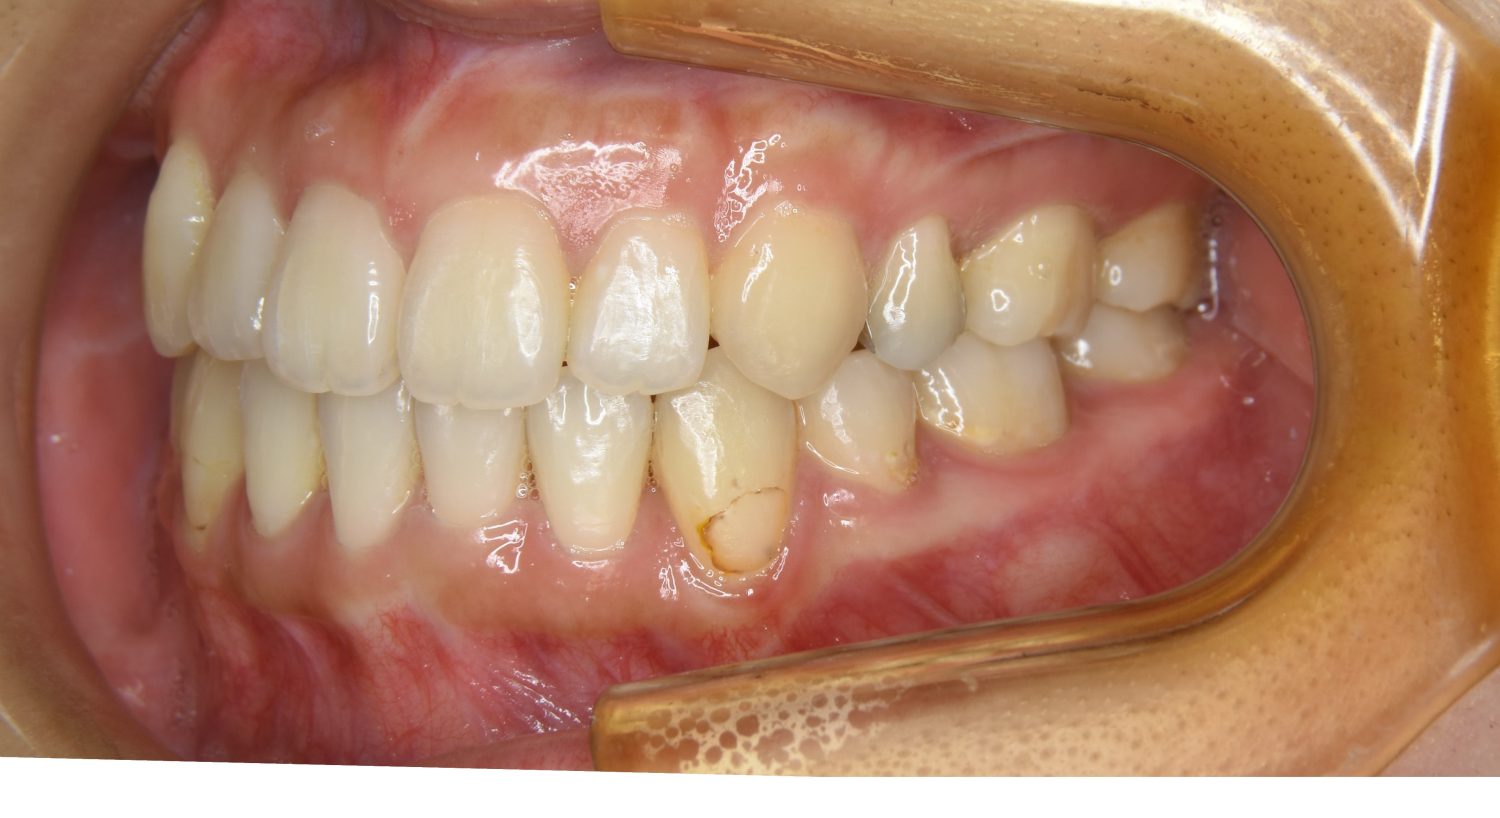

上顎前突の症例紹介②

Before

After

主訴

出っ歯を治したい。

治療内容

上顎両側第一小臼歯を抜歯し、上下ラビアルブラケット(唇側装置)にて治療を行いました。

治療費

1,000,000 円(税込)

治療期間

25ヶ月

通院回数

25回

想定されたリスク

※なし

丸山和宏先生

ピーススマイル矯正歯科

上顎前歯の前突により口元の突出が認められました。上の左右の第一小臼歯を抜歯し上顎前歯を後退させることで口元の突出感は改善し、咬合も良好な状態となりました。